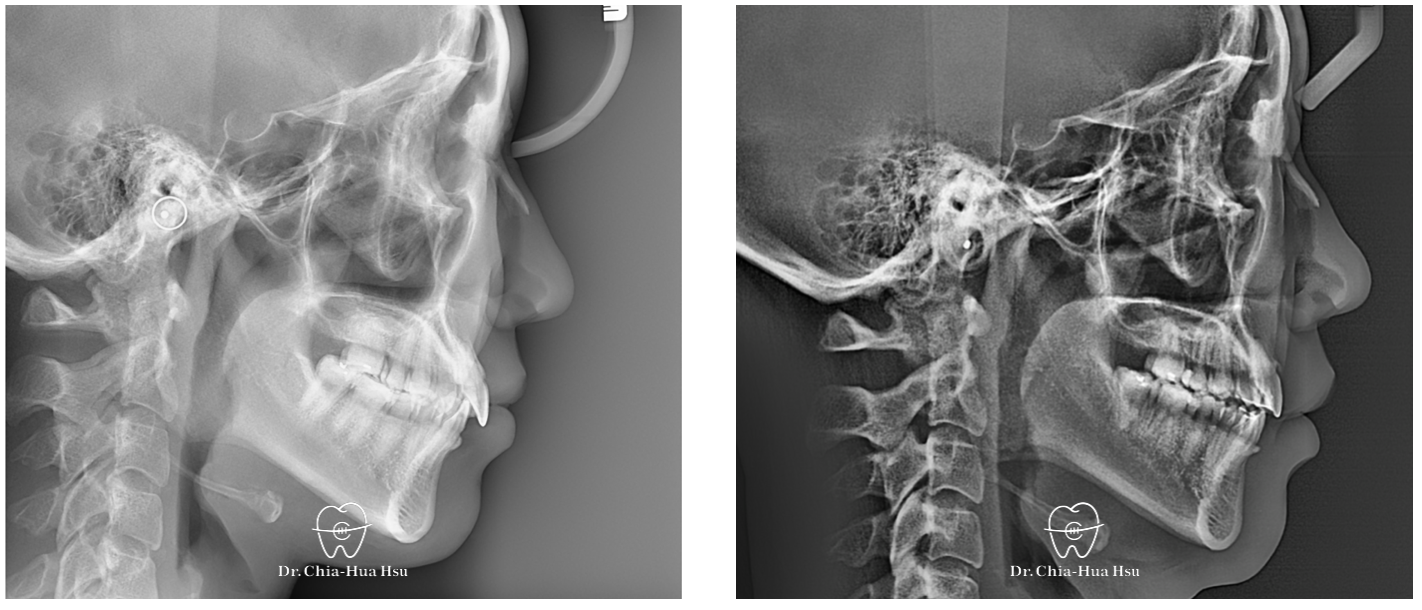

- 問題分析:患者除了暴牙、笑齦問題,有先天性缺失下顎門牙一顆以及上顎兩顆大臼齒,治療難度高。

- 治療方式:使用傳統金屬矯正器,並搭配上顎骨釘的使用,改善暴牙。另外,也利用電燒的方式進行牙齦修整術來改善笑齦。

- 治療結果:改善笑齦與暴牙,以及上下顎咬合關係 ; 然而,因為下顎先天性缺失三顆牙,上下牙齒比例與咬合對應上結果較為妥協。

治療前

治療後